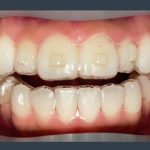

皆さま、こんにちは。 アルデブラン・デンタルクリニック神戸三宮院 歯科助手のYです。 今回は矯正治療の精密検査について詳しくご紹介します。 検査項目は以下となります。 ・レントゲン ・虫歯、歯周病のチェック ・口 […]